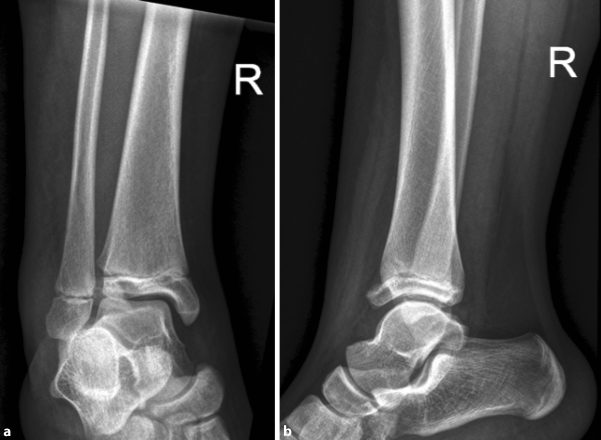

An exemplary case of a 14-year-old patient with a surgically treated Tillaux fracture is presented in Figs. 2 to 5 (Fig. 2a, b, X‑ray; Fig. 3a, b, CT scan; Fig. 4a, b, X‑ray after open reduction and screw fixation; Fig. 5a, b, X‑ray in two planes after screw removal).

Fig. 5

X-ray in two planes after screw removal in a 14-year-old patient (a anteroposterior view, b lateral view)

Bild vergrößern